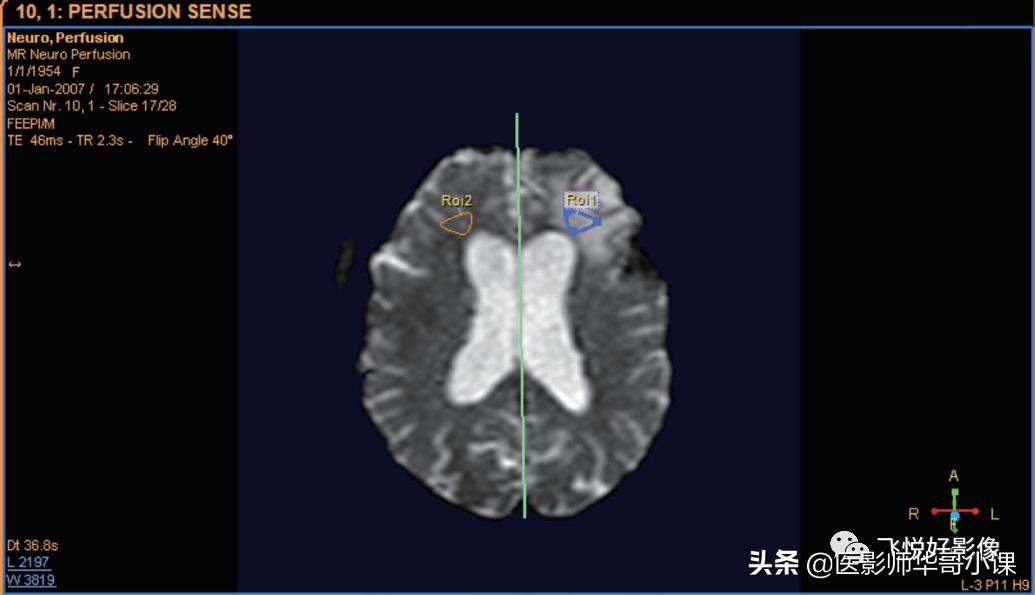

单击“显示镜射线”复选框,一个垂直镜线将显示在图像中间。拖动此线可将其移动或旋转。

图12.镜线

在绘制 ROI 时,可以启用 / 禁用镜线 ROI 的自动生成功能。单击“自动创建对侧 ROI”复选框。绘制 ROI,确定感兴趣区或者病变区域,完成后,将镜像绘制 ROI,自动创建对侧 ROI。